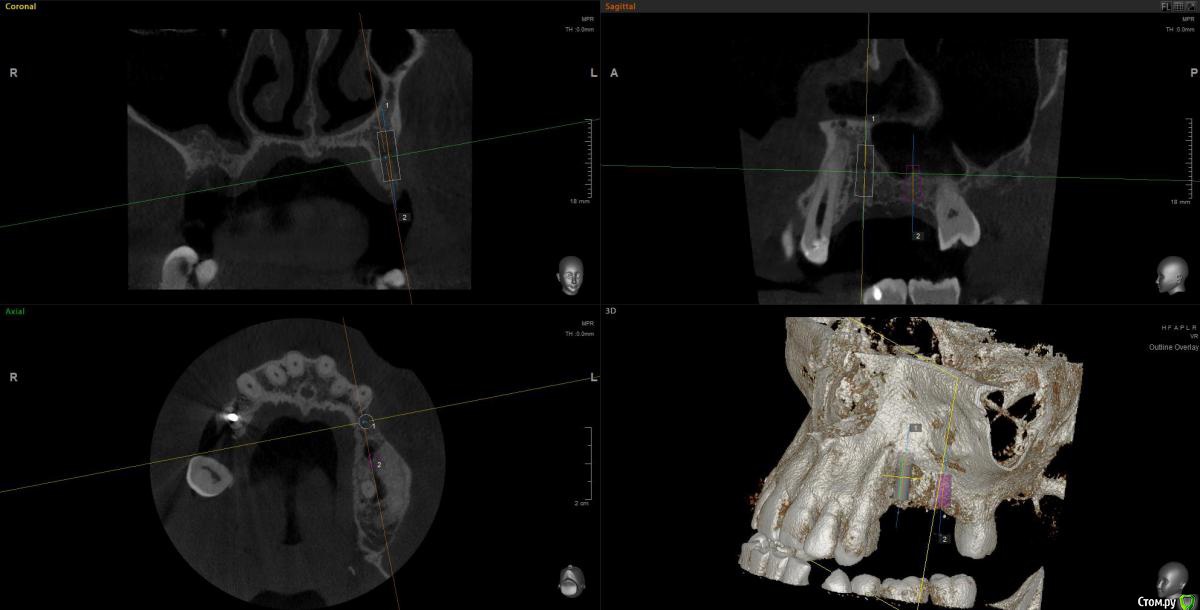

Kostoprav Опубликовано 28 августа, 2020 Поделиться Опубликовано 28 августа, 2020 остеоматрикс+ ауто, укрыто все лоскутом сверху без дополнительных мембран.сделал много таких работ на н\ч и на в\ч- результаты пока очень радуют. 8 Ссылка на комментарий

Александр07 Опубликовано 30 августа, 2020 Поделиться Опубликовано 30 августа, 2020 остеоматрикс+ ауто, укрыто все лоскутом сверху без дополнительных мембран.сделал много таких работ на н\ч и на в\ч- результаты пока очень радуют.Похоже на Смарт Билл, но не он, просто заглушкой фиксирована или переходник есть ? Ссылка на комментарий

Snow Doc Опубликовано 1 сентября, 2020 Поделиться Опубликовано 1 сентября, 2020 Кажется взяли кусок титановой сетки и прикрутили заглушкой к болту. А мы тут про сиартбилдеры, спейсеры... И так работает у кого-то) Ссылка на комментарий

АнтонТЛТ Опубликовано 1 сентября, 2020 Поделиться Опубликовано 1 сентября, 2020 Кажется взяли кусок титановой сетки и прикрутили заглушкой к болту. А мы тут про сиартбилдеры, спейсеры... И так работает у кого-то)А что спейсер на кт уже не видно?)) Ссылка на комментарий

Марья Моревна Опубликовано 1 сентября, 2020 Поделиться Опубликовано 1 сентября, 2020 А что спейсер на кт уже не видно?)) Я вижу и на фото.Антон, а Ваша клиника случайно не "Леонардо да Винчи" называется? )) Ссылка на комментарий